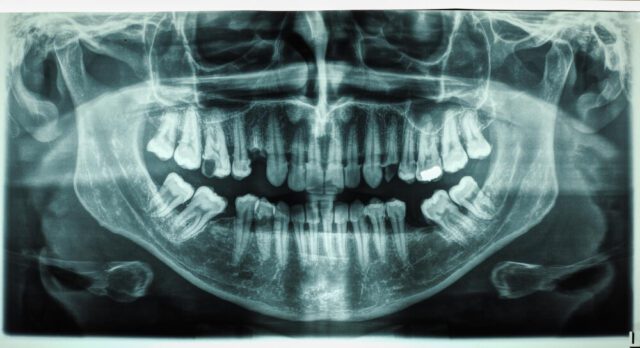

زراعة الأسنان والتركيبات عالية الجودة

تعتبر زراعة الأسنان هي الحل الأمثل لتعويض الأسنان المفقودة بشكل دائم. نقدم في مدونتنا إرشادات حول المراحل المختلفة لـ زراعة الأسنان، وتقنيات الزراعة الفورية، ومعلومات عن أنواع الزرعات المستخدمة (والتي نستخدم منها الأفضل عالمياً). كما نوضح كيفية العناية بـ التركيبات الثابتة والمتحركة لضمان استمراريتها لمدى الحياة.